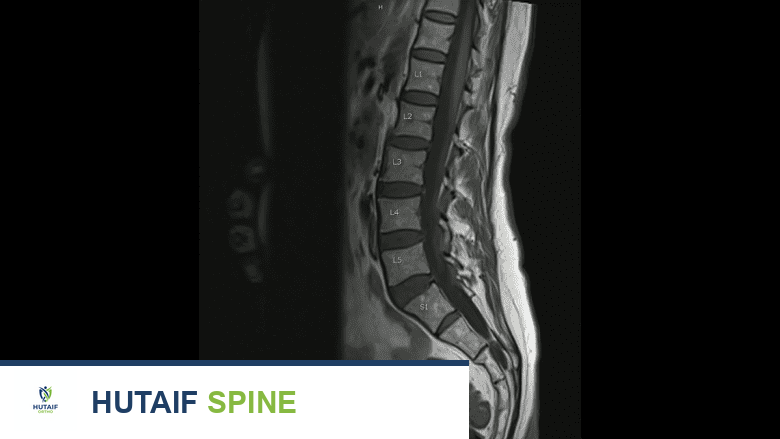

توفر فحوصات الرنين المغناطيسي صورًا للأطباء لتشخيص الألم وتخطيط العلاج ومراقبة التقدم.

تُنشئ اختبارات التصوير أو الأشعة أو التصوير الإشعاعي صورًا قياسية أو مفصلة لمناطق معينة داخل الجسم، مثل المفاصل والعظام والأقراص والأعضاء والأنسجة الرخوة. يستخدم الأطباء الصور التي يتم الحصول عليها من هذه الاختبارات لتحليل الأنسجة، لتشخيص السبب الكامن وراء الألم، أو تخطيط العلاج، أو مراقبة تقدم العلاج.

- التصوير بالرنين المغناطيسي (MRI scans): يُعد المعيار الذهبي لتصوير العمود الفقري لأنه يوفر صورًا مفصلة للغاية للأنسجة الرخوة، بما في ذلك الأقراص، الأعصاب، الحبل الشوكي، الأربطة، والعضلات. يُستخدم لتشخيص الانزلاق الغضروفي، تضيق القناة الشوكية، الأورام، العدوى، والتهاب المفاصل.